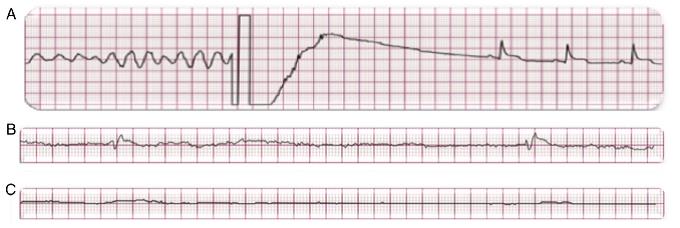

El tratamiento del paro cardiaco súbito secundario a FV o TV es la desfibrilación ventricular31, y cuanto más temprano se realice, mayor será la posibilidad de revertir a ritmo sinusal (Fig. 2). Al primer minuto, el éxito de la desfibrilación ventricular es superior al 90%, y desciende 7-10% por minuto sin reanimación cardiopulmonar (RCP); con RCP la probabilidad de revertir a ritmo sinusal desciende, de un 3-4% por minuto32. La RCP prolonga la ventana de tiempo para poder realizar desfibrilación exitosa33. Se deberá realizar la cadena básica de supervivencia ante un paciente en paro cardiaco. Dicha cadena implica la detección temprana del paciente y activación del sistema de urgencia médica, RCP temprana, desfibrilación temprana, cuidados avanzados tempranos y cuidados tempranos posreanimación. Al realizar todos los eslabones de la cadena de supervivencia dentro de los primeros 5 min del colapso, se mejoran de forma significativa las tasas de supervivencia de estos pacientes31-34 (Fig. 3). La colocación de desfibriladores externos automáticos en sitios públicos junto con la realización de maniobras básicas de RCP por el observador de una víctima de paro cardiaco súbito ha demostrado que mejora significativamente la supervivencia, por lo que se recomienda ampliamente la colocación de desfibriladores externos automáticos y el entrenamiento al público en maniobras básicas de RCP en escuelas, aeropuertos, gimnasios, empresas y lugares estratégicos de la comunidad con alta densidad poblacional35. El desfibrilador automático implantable (DAI) es un equipo con alta posibilidad de revertir a ritmo sinusal un episodio de TV o FV ya que puede desfibrilar en menos de 15 seg una de estas arritmias36-39. La FV produce una contracción irregular y caótica del miocardio ventricular, con la consecuente incapacidad del corazón para mantener el flujo sanguíneo corporal; de no ser revertida a ritmo sinusal, pasará a asistolia y posteriormente causará la muerte del paciente32,36. En la Figura 4 se muestran ejemplos de FV, ritmo agónico y asistolia.